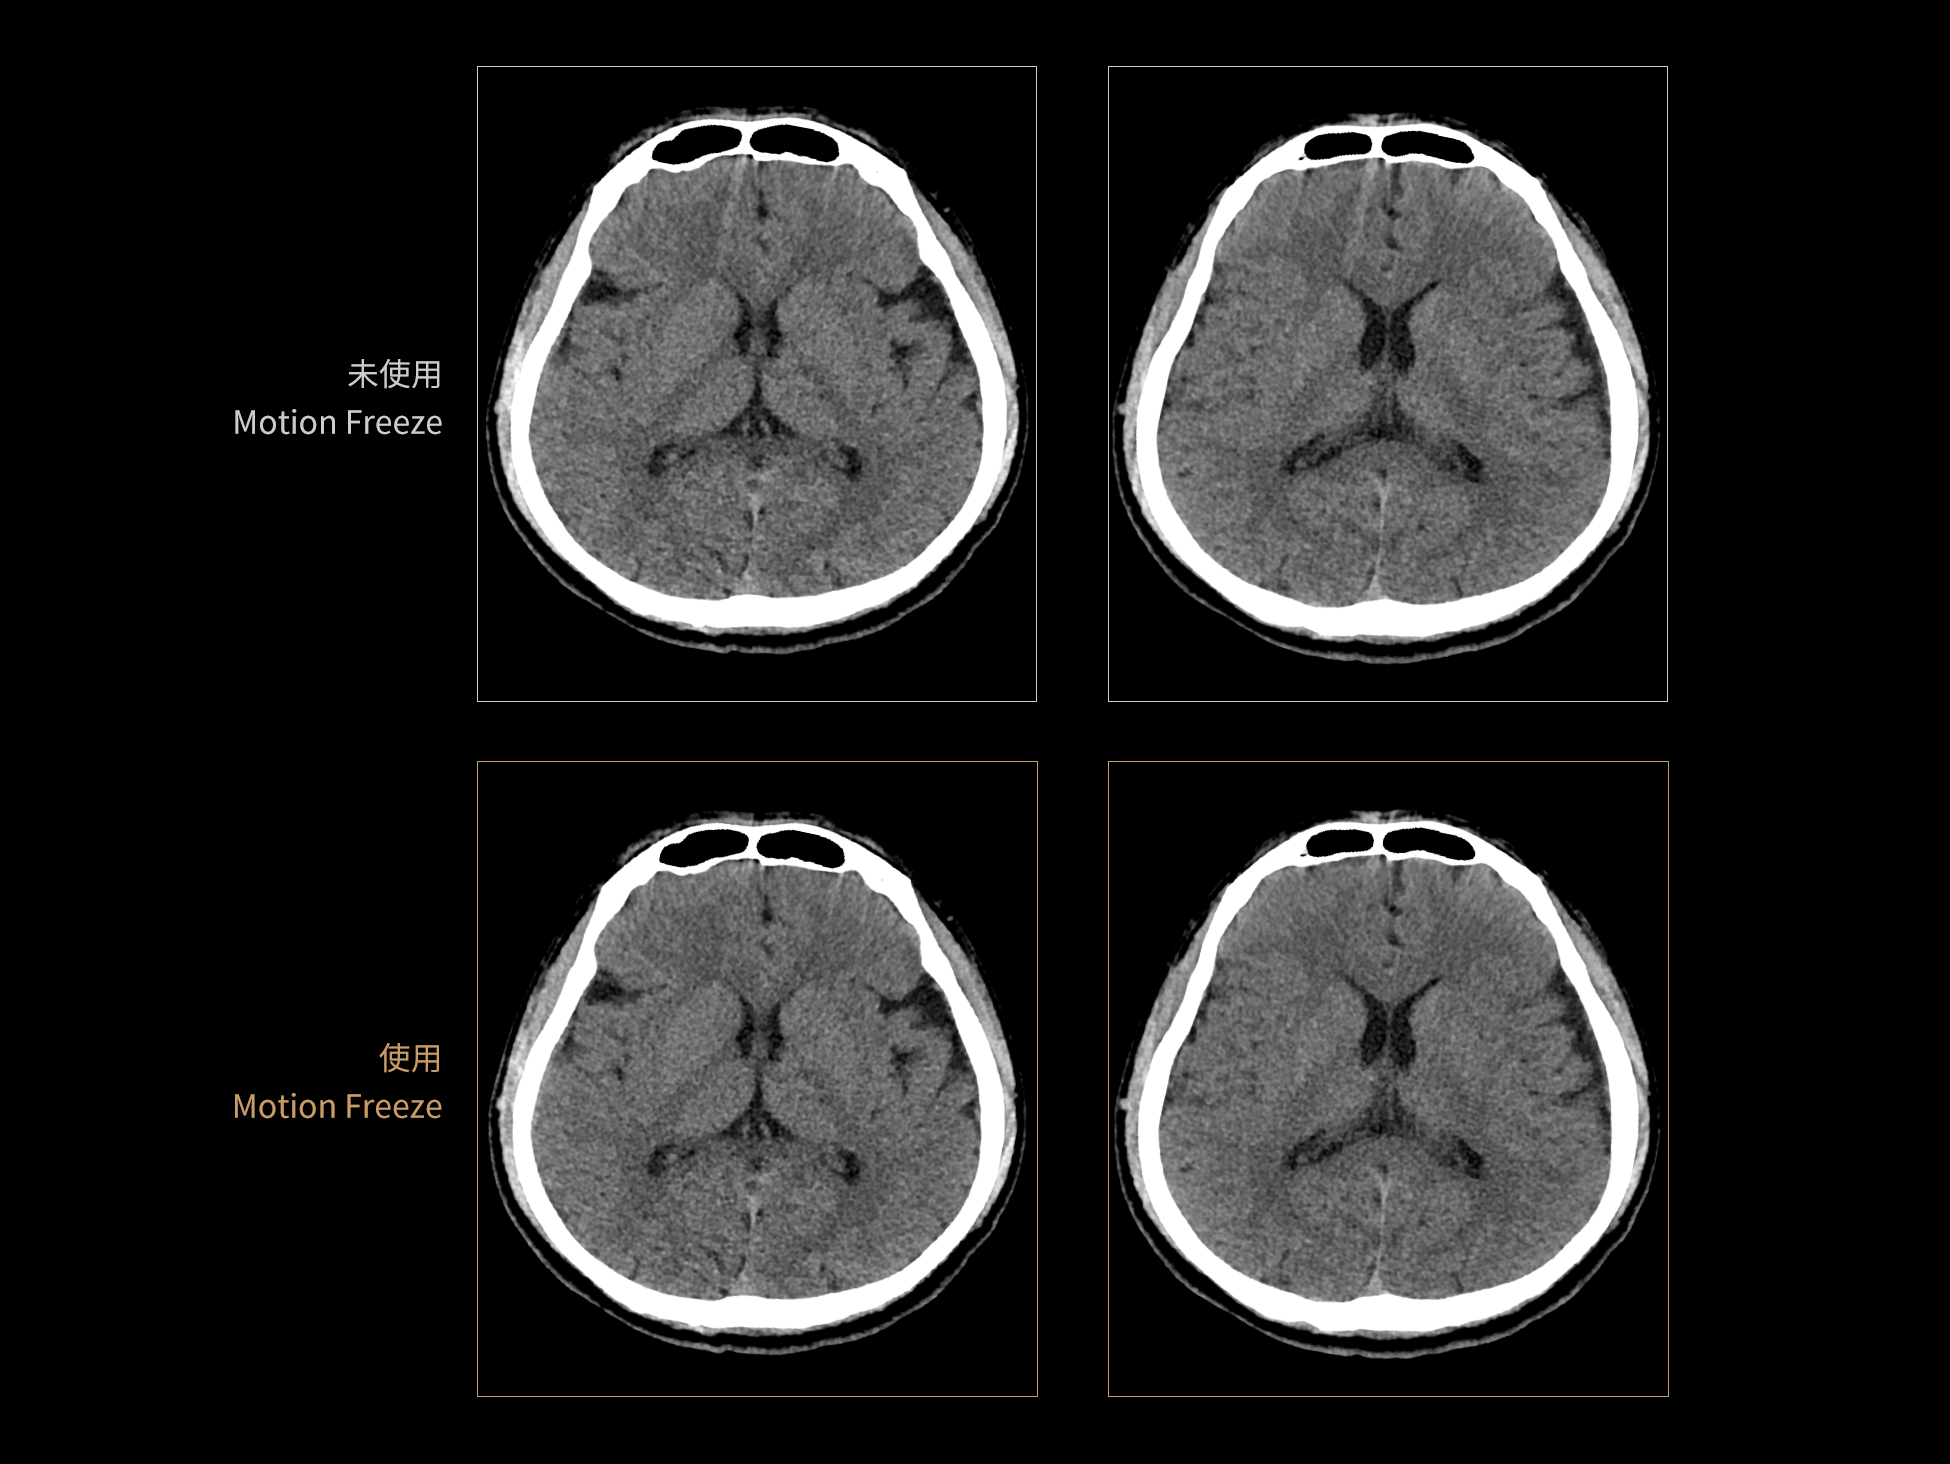

uCT 868 搭载联影最新一代 uSense 人工智能平台,将智能化深度融入 CT 扫描全流程,从感知细微生理运动到精细结构探测,再到多场景诊疗优化。以 AI 为核心驱动力,uSense 重塑成像各环节,打造高效、高清的智慧扫查体验。在心脏成像领域,uSense 结合宽体探测器、心脏专研AI重建算法与AI冠脉运动追焦技术,在保持低剂量的同时,有效抑制运动伪影,精准呈现软斑块、混合型斑块及支架细节,助力冠脉成像惠及更多患者。针对多科室疾病临床应用场景,uSense 平台提供全方位的智能解决方案:包括头部运动伪影智能校正、金属植入物伪影抑制、扫描视野扩展等先进算法。这些创新技术使 uCT 868 能够构建覆盖全场景的智能诊疗体系,持续拓展 AI 赋能医学影像的边界。